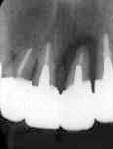

| 初診時 Dental写真 | 5年後(手術時) | 術後6年 |

![]() |

| 1|感染根管治療、2|著変なし 32歳 女性 |

2|近心側の骨吸収が著しい FOp+HAP施行 |

ココまでは経過良好 こののちアパタイト流出 |

| 術後15年(初診より20年) | 抜去歯牙 |

| アパタイトは完全に排出され排膿も著しい | 骨欠損部分に相応して歯石沈着が著しい |

処置および経過:

1|感染根管治療および歯冠補綴終了後来院が途絶え、5年後に再び来院。

2|近心側の骨吸収が著しいので、抜髄の上歯周外科処置(FOp+HAP)を施行し補綴物

による連結固定を行ってメインテナンスに移行したが、数か月後には来院が途絶えてしまった。

その後も約5年ごとに来院され、そのたびに上顎臼歯部・下顎臼歯部の歯周外科処置を行い

しばらくはメインテナンスに応じるが結局来院が途絶えてしまうパターンを繰り返す。

2|の手術を行って15年後、いよいよ排膿が著しくなり動揺も著しくなったので歯牙

保存不可能と判断して抜歯。

考察:

手術を行う前の5年間の歯槽骨吸収の速度から考えると、15年間機能させた臨床的意義は十分

あった症例だと思う。また、術後6年目までは補填した人工骨も十分機能したようであるが、

その後はアパタイト自体が汚染され異物と認識される状態となり排膿と伴に徐々に排泄された

ことはアパタイトの限界を思わせる臨床経過であった。

メインテナンスをもっと徹底して行っていたとすれば、抜歯の時期をあと5年は遅らせることが可能

だったと考えられる。とはいっても数年に1度以上はスケーリングを行っていたが、それだけでは

一旦手術した部位の歯石沈着を防ぎ切れないことを物語る。他のケース同様、抜去歯牙に

沈着した歯石の量には圧倒される。